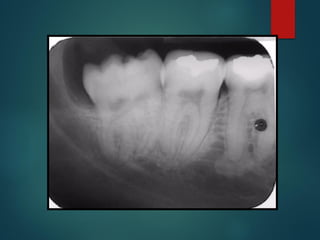

Lesiones

Periapicales

Clasificación de las

Lesiones Periapicales

Desde el punto de vista rx

 Línea periodontal apical engrosada

 Granuloma

 Quiste

 Osteítis

 Osteítis condensante

Linea Periodontal

Apical Engrosada

Línea Periodontal

Causas

 Periodontitis apical

crónica

 Trauma oclusal

 Distorsión por

amplitud

 Sumación de

absorciones